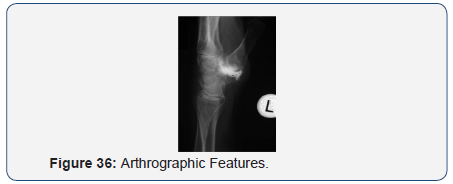

Arthrographic Features

- Distinct Joint Space - 25 wrists

- Comm. with midcarpal joint - 10 wrists

- Comm. with radiocarpal joint - 2 wrists

- Comm. with distal RU joint - 1 wrist

- Comm. with tendon sheaths - 4 wrists

- Contour-Irregular & small - 16 wrists

- Regular & larger - 9 wrists (Figures 33-36).

- Distinct joint space

- Small & Irregular within 6 months of Surgery

- Large & Regular thereafter